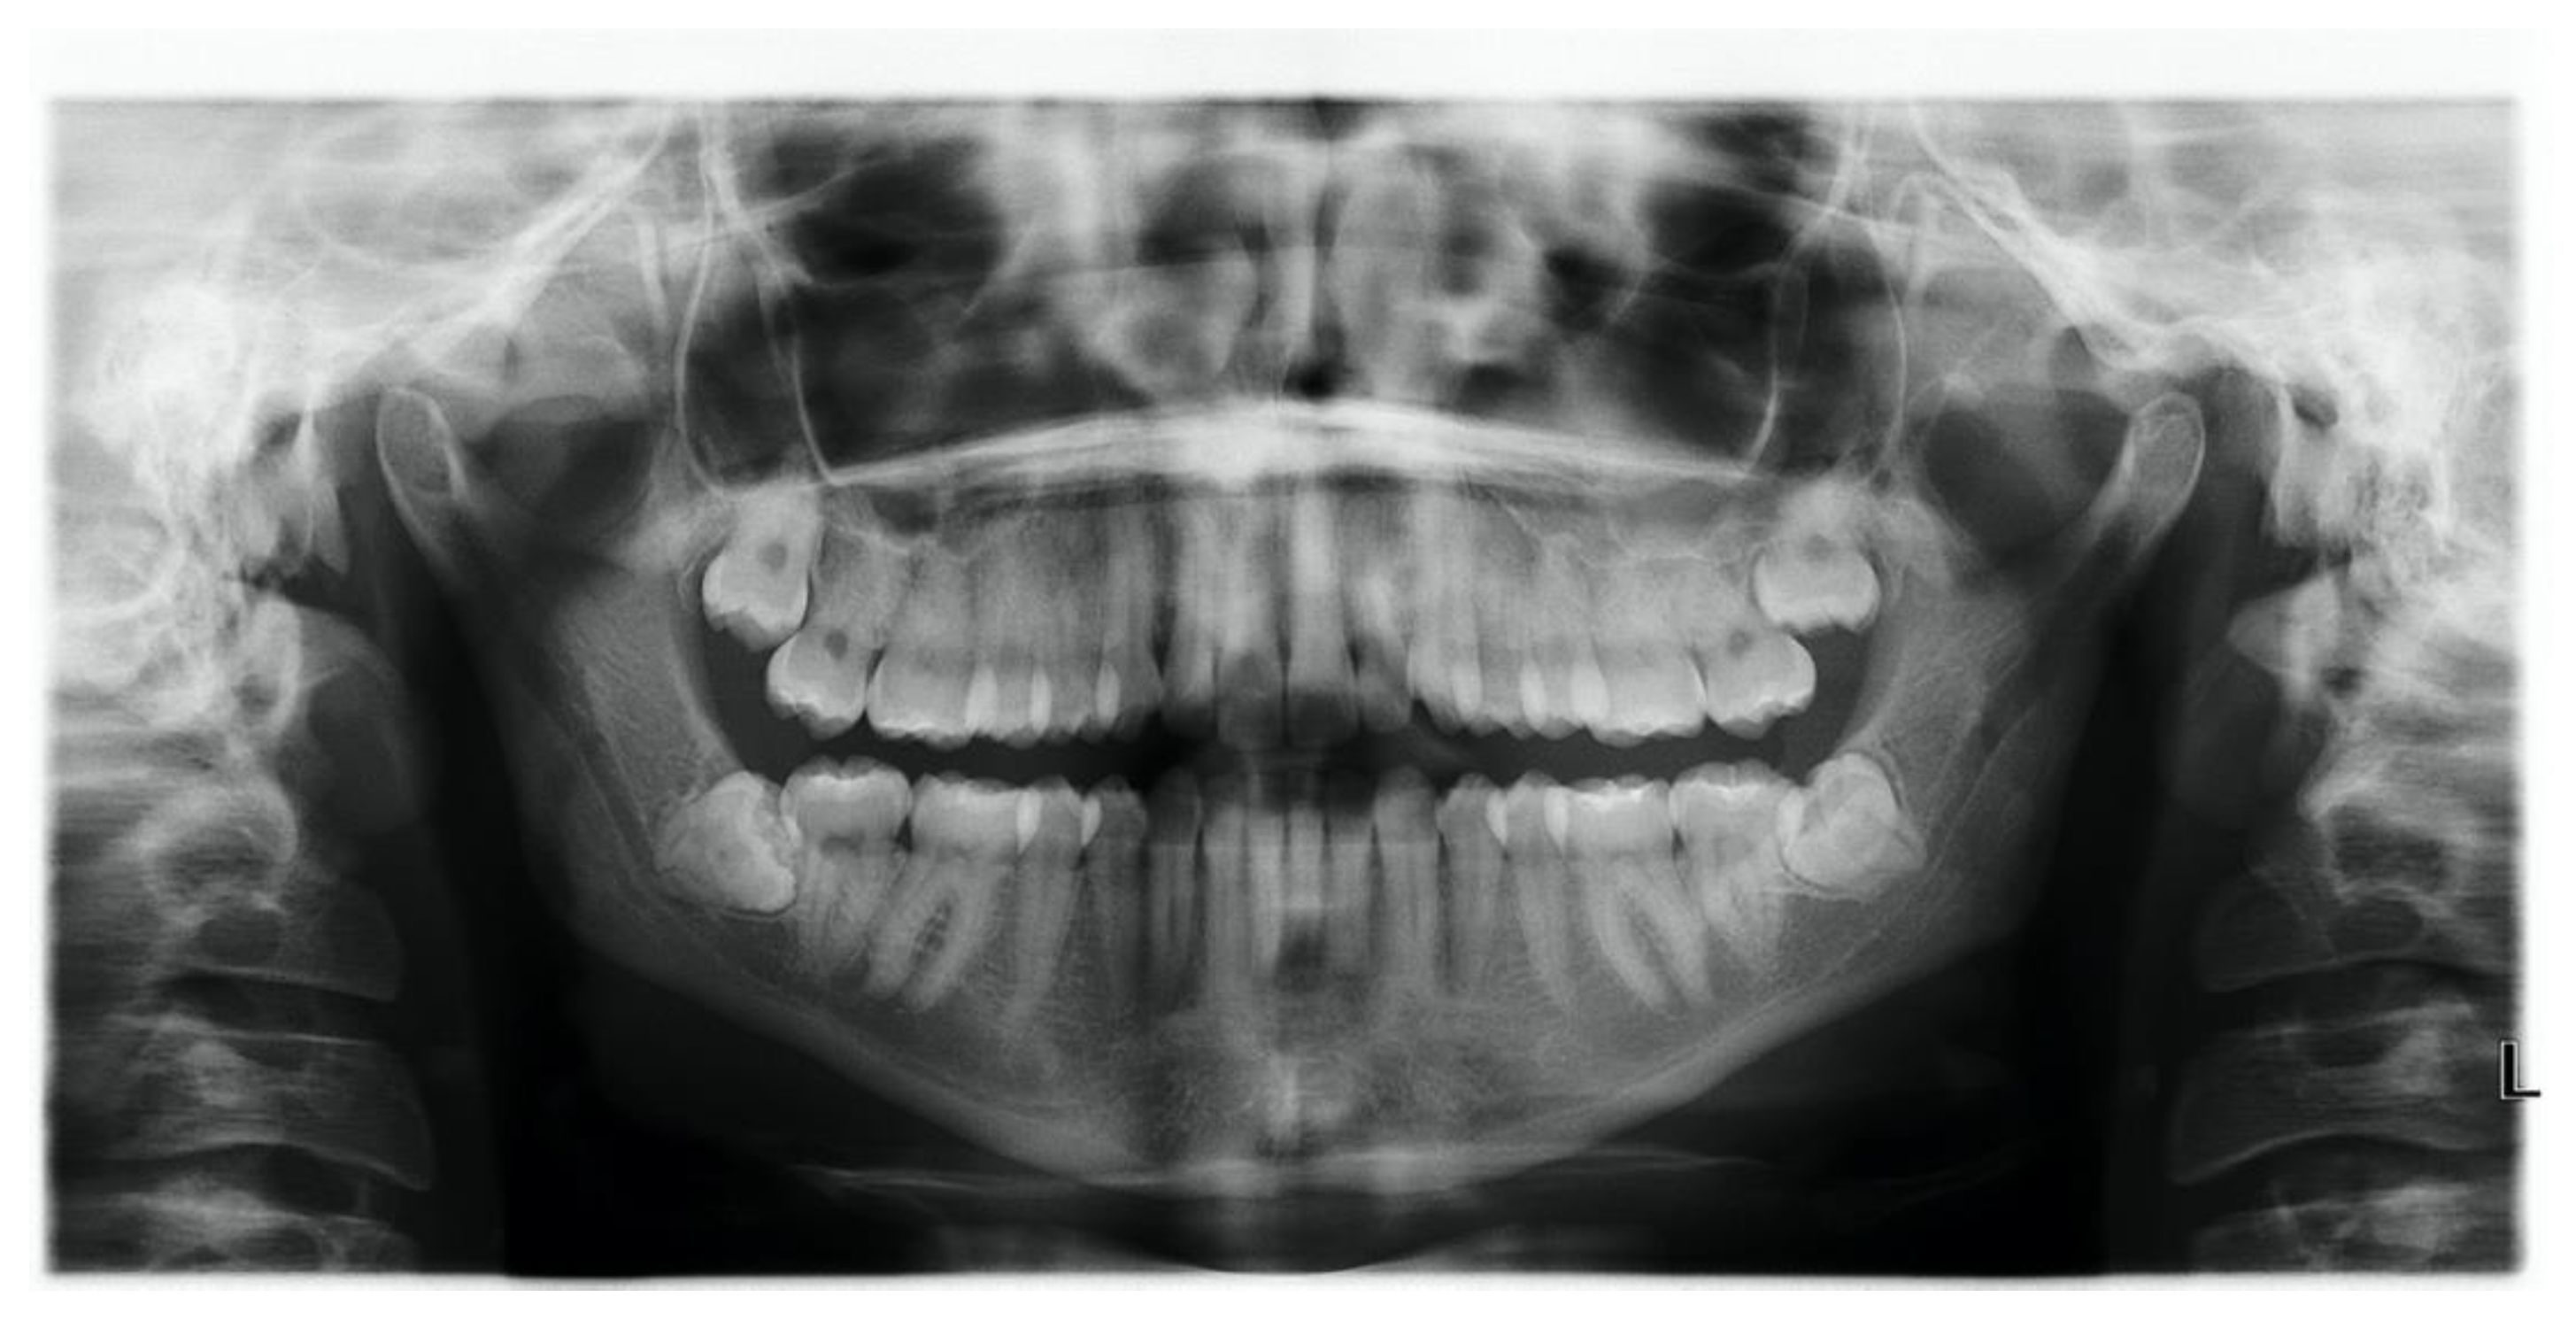

3.1. Case 1: Perialveolar Infection